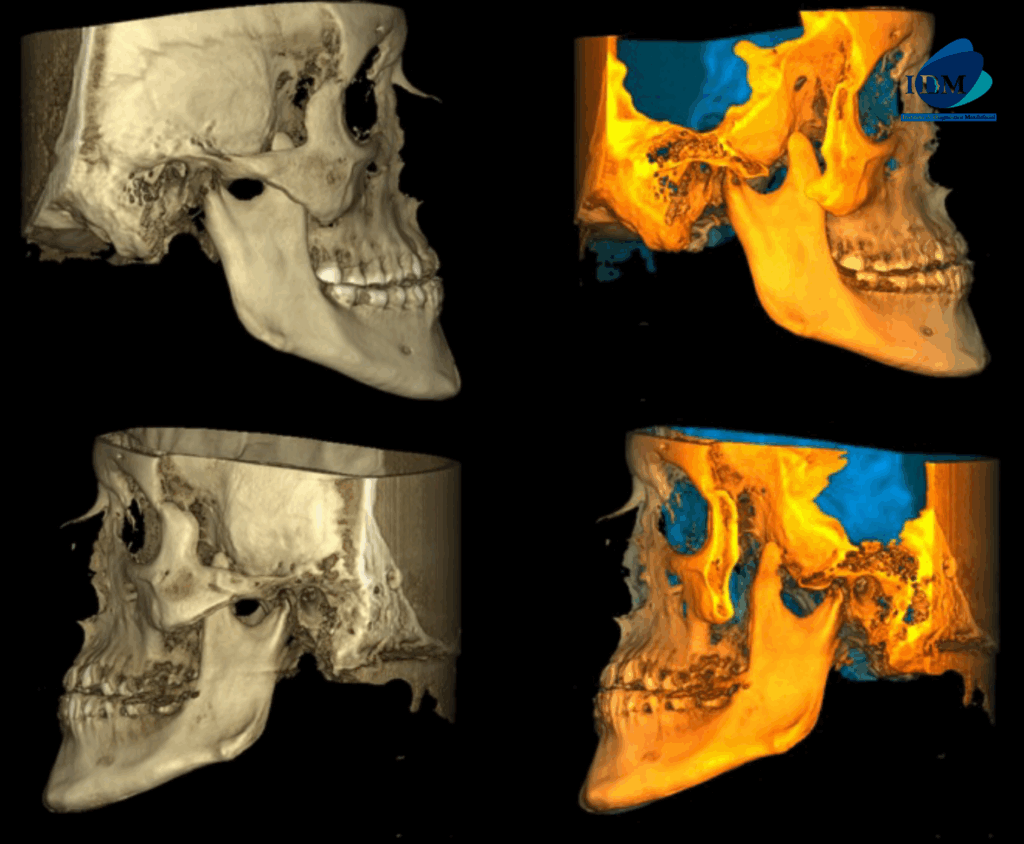

A la evaluación de la tomografía computarizada se puede observar el aumento de la longitud cefalo caudal de la apófisis coronoides bilateral que se extiende superior al borde del arco cigomático.

RECONSTRUCCIÓN 3D

La herramienta más útil para su diagnóstico es la tomografía con reconstrucción tridimensional, y su tratamiento de elección es quirúrgico mediante la coronoidectomía.